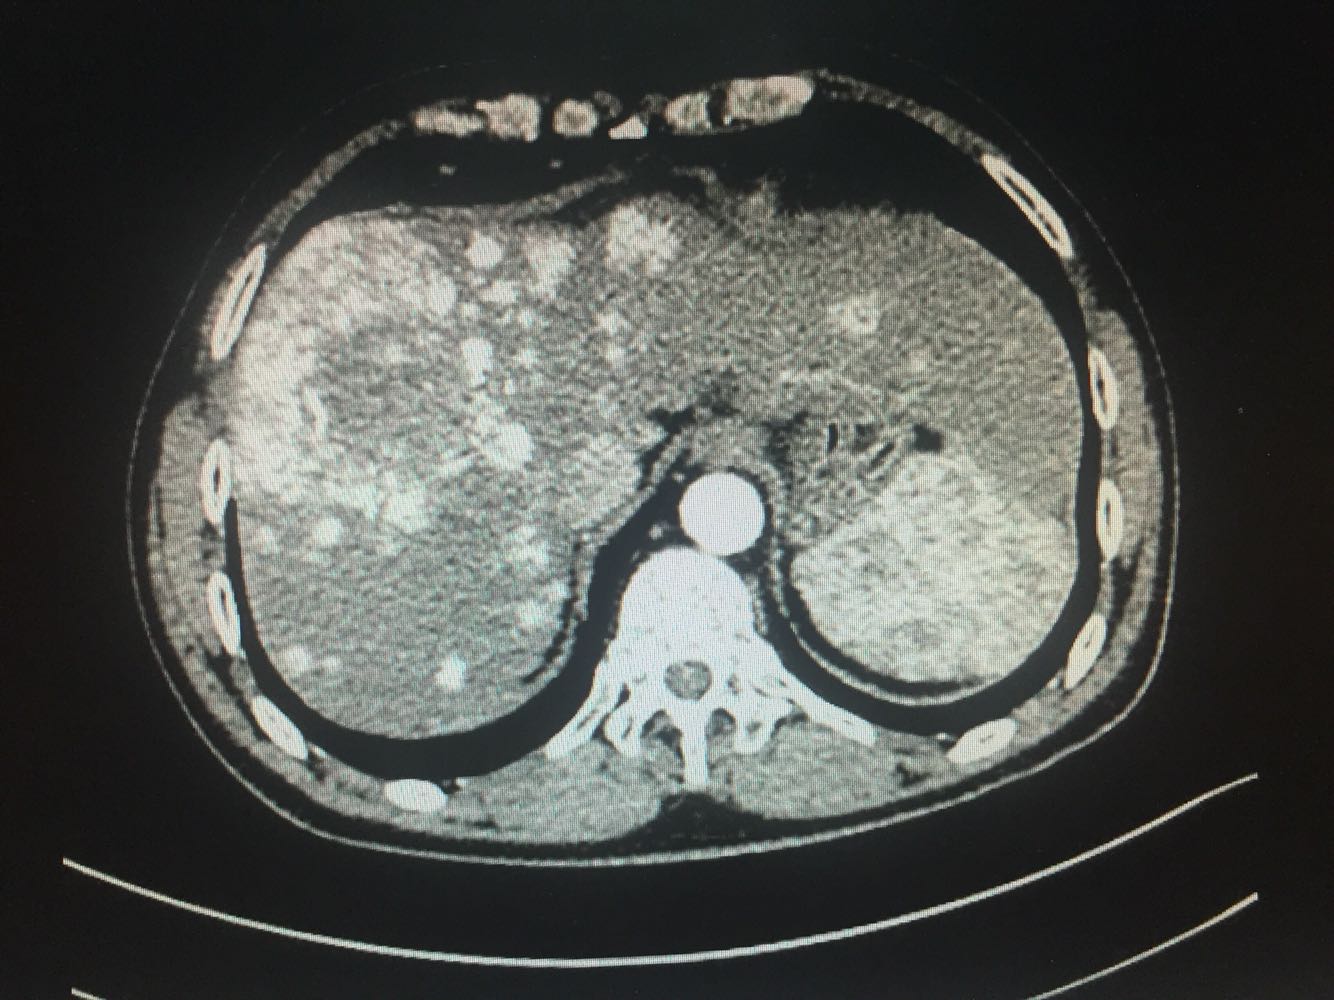

查体:体温,36摄氏度,脉搏:60次/分,呼吸,19次/分、血压,115/70mmhg,发育正常,营养欠佳,皮肤黏膜,色泽正常,双侧眼睑正常,双侧巩膜无黄染,口唇红润,双肺呼吸音清晰,心率60次/分,心律齐,心音有力,无病理性杂音。右上腹部饱满,中上腹压痛明显,肝脏肋下2cm触及,质地硬,触痛阳性,脾肋下2cm触及,移动性浊音阴性,肠音正常,双下肢无水肿 化验:血常规:白细胞计数2.9*10~9/L,中性粒细胞1.4*10~9L,红细胞计数4.03*10^12L,血小板计数76*10^9/L;生化全套。血糖4.67mol/L,总蛋白81.0g/L,白蛋白40.9g/1L,丙氯酸氨基转移酶256U/L,天门冬氨酸氨基转移酶182U,总胆红素22.0umol/L,胆碱酯酶4479U/L,Y-谷氨酰基转移酶137U/L;传染病9项:乙型肝炎病表面抗原阳性/6380,乙型肝炎病毒e抗体阳性/0.004,乙型肝炎病毒核心抗体阳性/0.008 肿瘤标志物:甲胎蛋白415.50ng/ml,乙型肝炎病毒DNA测定2.06E+07IU/ml CT:1.考虑肝右叶巨块型肝癌伴肝内多发转移,2.肝门部及腹膜后、心隔角旁小淋巴结。3.肝小囊肿。4.肝左叶増大。5.肝脏钙化灶。6.副牌。7.双肾微小囊肿

乙肝肝硬化,原发性肝癌,保肝抗病毒治疗,及TACE

出院一月后复查,行增强CT扫描,肿瘤明显缩小,肝功能正常,乙肝病毒复制转阴,建议继续口服恩替卡韦抗病毒治疗